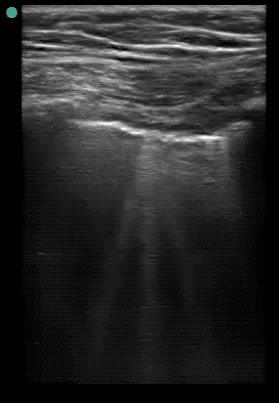

The following ultrasonographic signs are suggestive of pulmonary edema:

• Multiple B-lines (>2) between two costae in more than one view bilaterally

The following ultrasonographic signs rule out pulmonary edema:

• Absence of multiple B-lines between two costae in more than one view bilaterally